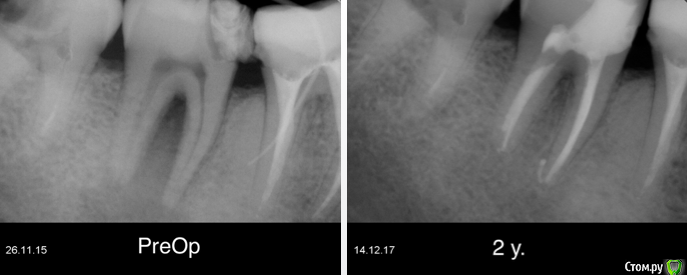

Гарриевич Опубликовано 22 декабря, 2017 Поделиться Опубликовано 22 декабря, 2017 (изменено) админы, если уже создавал такую тему, объедините пожалуйста абсолютно бессимптомный зуб, пациента ничего не беспокоило кроме... да нет, вообще ничего не беспокоило. Лечение в два посещения через гидроксид кальция. Обтурация инжектором. Будут вопросы спрашивайте, каких то еще особенностей сразу не вспомню PS сроки наблюдения 10 месяцев и два года Изменено 22 декабря, 2017 пользователем Гарриевич 8 Ссылка на комментарий

Гарриевич Опубликовано 15 сентября, 2019 Автор Поделиться Опубликовано 15 сентября, 2019 полное заживление, осмотр через 3 года 5 Ссылка на комментарий